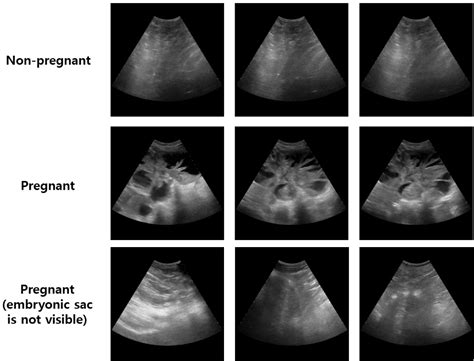

An echo in pregnancy, also known as a fetal echocardiogram, is an ultrasound test that focuses on the baby's heart. This specialized ultrasound uses sound waves to create detailed images of the heart's structure and function. The procedure is typically performed between 18 and 24 weeks of pregnancy, although it can be done earlier if there are concerns about the baby's heart health.